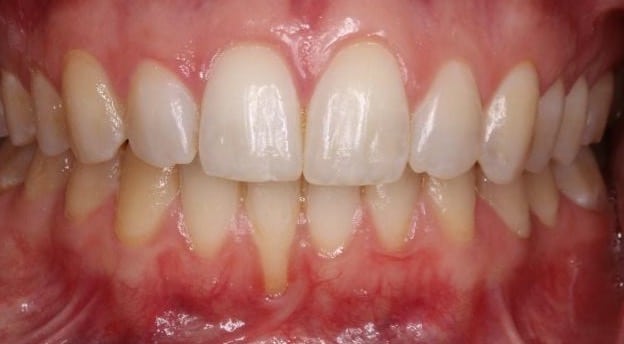

Coronally Advanced Flap with connective tissue graft

This method is commonly used to achieve total root coverage in isolated and multiple recession sites. This method requires harvesting a connective tissue graft from the palate. This graft is then sutured onto the defect, and it is subsequently covered by a coronally advanced flap.

Figure 2. Surgical management of lower anterior recession using a coronally advanced flap and subepithelial connective tissue graft.